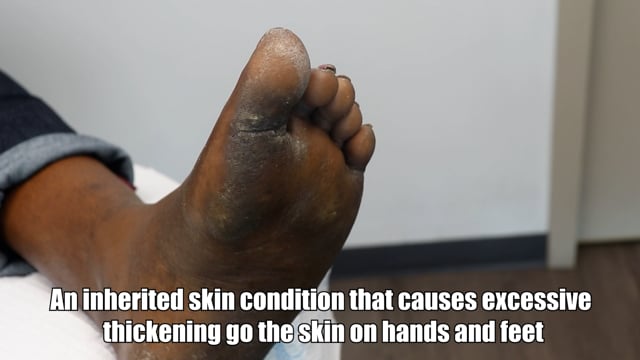

Did it grow back on his foot? ***diabetic foot growth update***

Stories